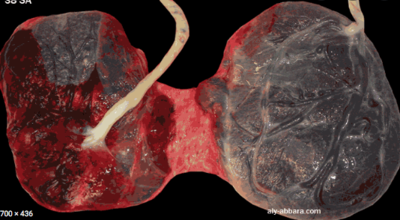

Je pense que le meilleur moyen pour comprendre est de te montrer clairement une photo pour que tu visualises, désolée c'est un peu dégueu mais au moins c'est clair :giggle: . Je le mets dans "afficher" pour les âmes sensibles :

Capture d’écran 2022-01-05 à 13.47.01.png

Sur cette photo tu vois bien qu'on a bien 2 placenta séparés et donc 2 cavités amniotiques séparés donc on est bien dans un cas de placenta bi-chorial bi-amniotique. MAIS on a une petite membrane inter-placentaire = entre les 2 placentas qui permet de les fusionner. Les 2 placentas se retrouvent donc fusionnés (car ils ne peuvent plus se décoller) et séparés (car une petite membrane est entre les 2 et qu'on est bien dans une placenta bichorial).

Si on avait pas cette membrane on serait dans le cas de placenta bi chorial bi amniotique avec 2 placentas complétement séparés.

On a donc bien 2 cas de placenta BI-chorial BI-amniotique :

- le cas où les placentas sont séparés (sans membrane inter-placentaire)

- le cas où les placentas sont fusionnés mais séparés par une membrane inter-placentaire